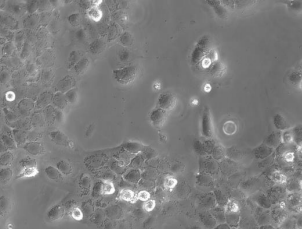

CaSki(人宫颈癌肠转移细胞)

CaSki细胞是从小肠肠系膜转移灶的细胞中建立的。据报道,CaSki细胞含有完整的HPV-16(每个细胞大约600个拷贝)和HPV-18相关序列。

细胞形态

上皮细胞样

细胞类型

肿瘤细胞

生长特性

贴壁细胞